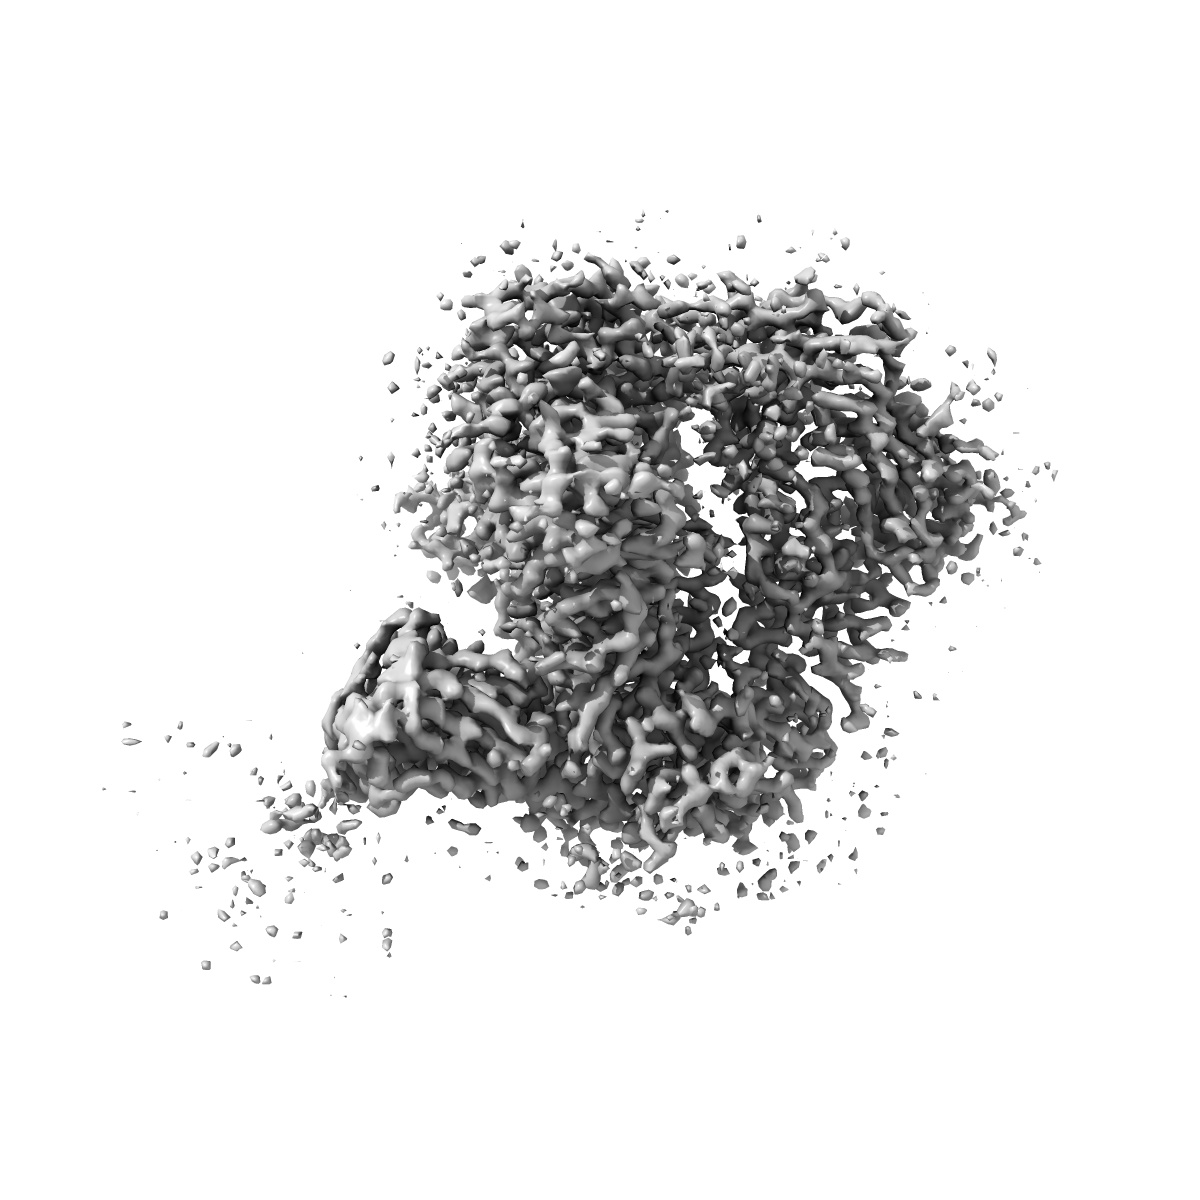

BG505 Boost2 SOSIP.664 in complex with NHP polyclonal antibody FP3

Single-particle3.5 Å

Sample: BG505 Boost 2 in complex with NHP Polyclonal Antibody FP3